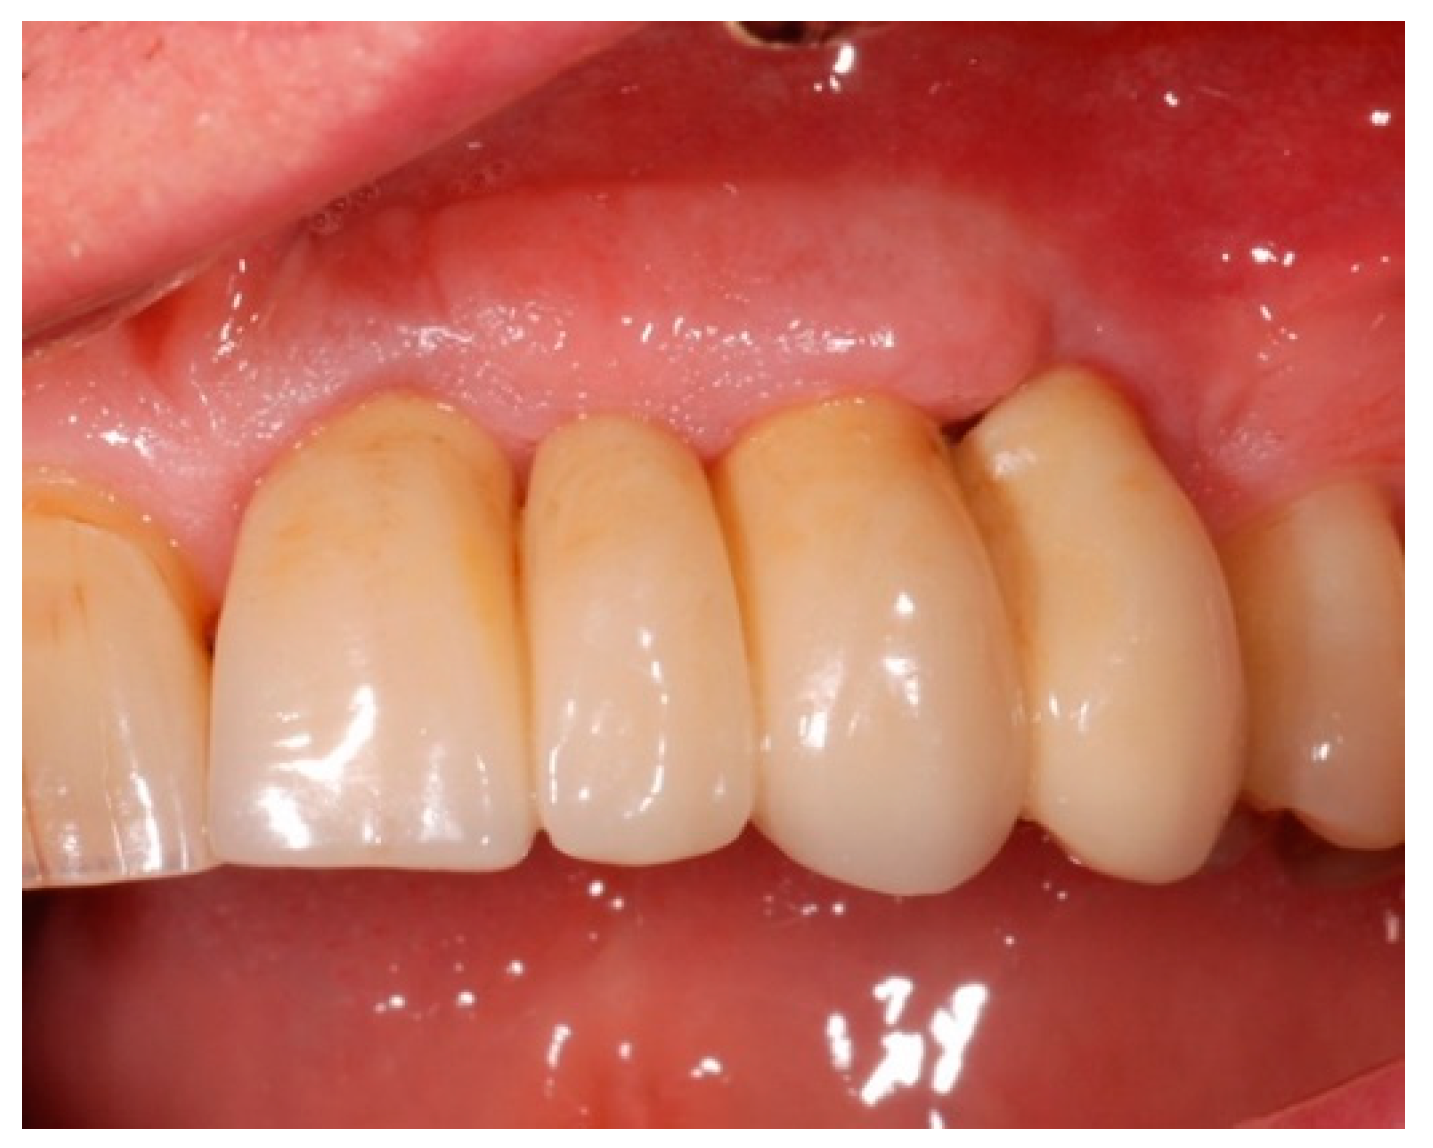

4.4. Study Protocol and Treatment

4.5. Test Substances and Administration